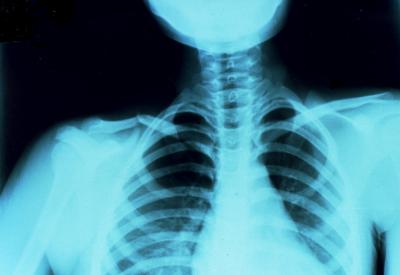

(鎖骨骨折)